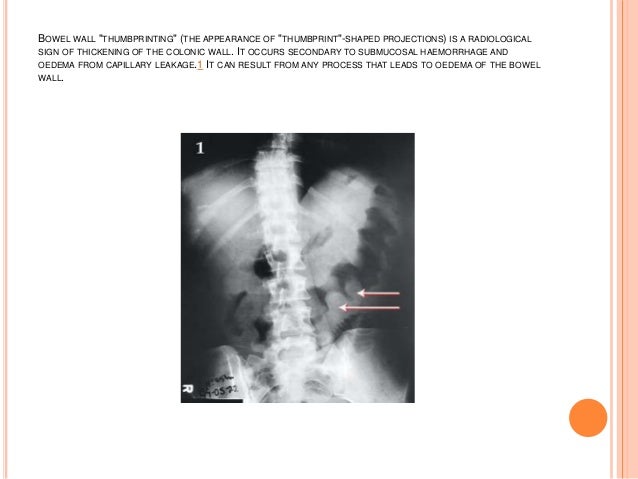

Radiology Review Plain Films Of Abdomen Ppt Video Online Download